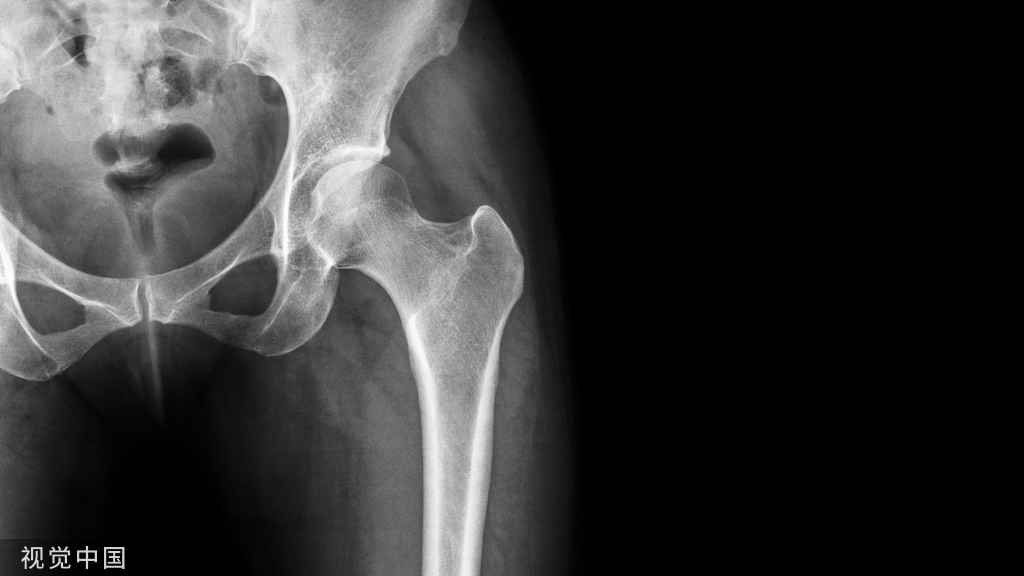

经皮椎体成形术及经皮椎体后凸成形术都属于治疗疼痛性椎体压缩性骨折的微创技术,与 PVP 不同的是,PKP 在注入骨水泥之前首先利用可扩张性球囊或其他装置置入椎体内并膨胀,从而尽量恢复椎体的高度并降低推注骨水泥的压力。

经皮椎体成形术( percutaneous vertebroplasty,PVP)及经皮椎体后凸成形术( percutaneous kyphoplasty,PKP)都属于治疗疼痛性椎体压缩性骨折的微创技术。

两者都是通过经皮穿刺的方法向椎体内注入骨水泥材料,以达到消除骨折微动、增强椎体的力学强度与缓解腰背疼痛的目的。

与 PVP 不同的是,PKP 在注入骨水泥之前首先利用可扩张性球囊或其他装置置入椎体内并膨胀,从而尽量恢复椎体的高度并降低推注骨水泥的压力。